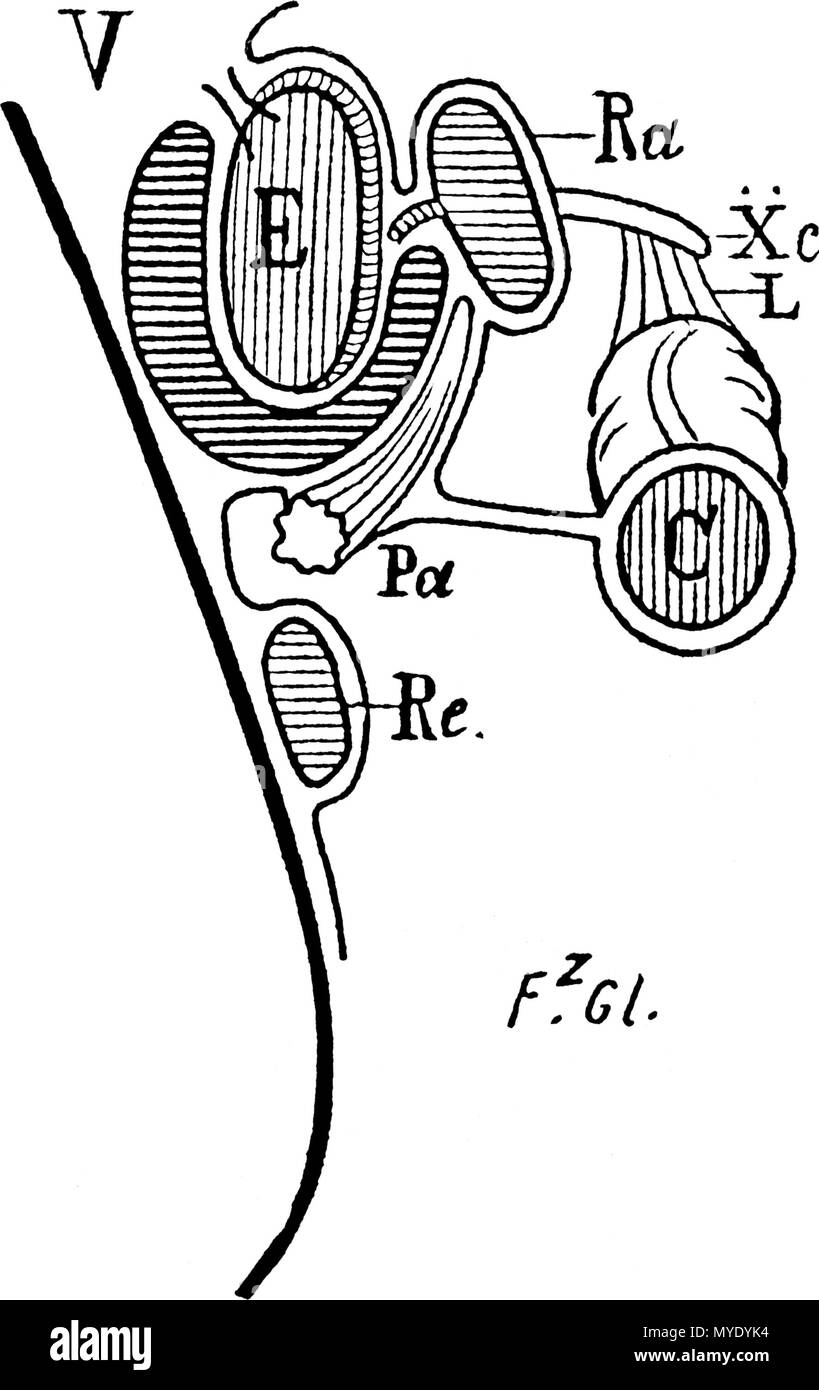

. Français : V, Au niveau de la grosse tubérosité. Le côlon n'a plus de rapport avec l'estomac. Ra, rate; Pa, pancréas ; Re, rein; Xc, 10e côte ; L, ligament pleuro-colique. . 1885 (1905). Fz. Glénard 179 FGelenardDe lEnteroptoseLyon medical1885 Stock Photohttps://www.alamy.com/image-license-details/?v=1https://www.alamy.com/franais-v-au-niveau-de-la-grosse-tubrosit-le-clon-na-plus-de-rapport-avec-lestomac-ra-rate-pa-pancras-re-rein-xc-10e-cte-l-ligament-pleuro-colique-1885-1905-fz-glnard-179-fgelenardde-lenteroptoselyon-medical1885-image189006472.html

. Français : V, Au niveau de la grosse tubérosité. Le côlon n'a plus de rapport avec l'estomac. Ra, rate; Pa, pancréas ; Re, rein; Xc, 10e côte ; L, ligament pleuro-colique. . 1885 (1905). Fz. Glénard 179 FGelenardDe lEnteroptoseLyon medical1885 Stock Photohttps://www.alamy.com/image-license-details/?v=1https://www.alamy.com/franais-v-au-niveau-de-la-grosse-tubrosit-le-clon-na-plus-de-rapport-avec-lestomac-ra-rate-pa-pancras-re-rein-xc-10e-cte-l-ligament-pleuro-colique-1885-1905-fz-glnard-179-fgelenardde-lenteroptoselyon-medical1885-image189006472.htmlRMMYDYK4–. Français : V, Au niveau de la grosse tubérosité. Le côlon n'a plus de rapport avec l'estomac. Ra, rate; Pa, pancréas ; Re, rein; Xc, 10e côte ; L, ligament pleuro-colique. . 1885 (1905). Fz. Glénard 179 FGelenardDe lEnteroptoseLyon medical1885